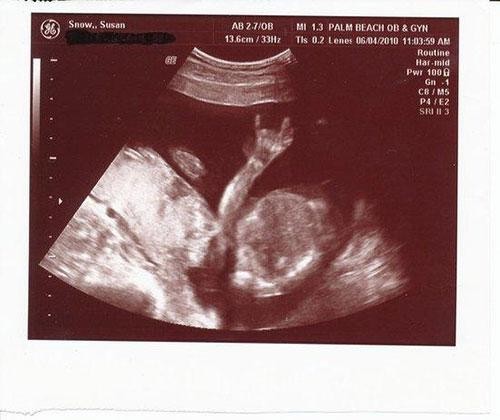

Bebeğin cinsiyetini öğrenmeye gitmişlerdi ama...

İşte bebek ultrasonlarında çekilen ve bazı anne babalara mini kalp krizi geçirten bebek fotoğrafları!